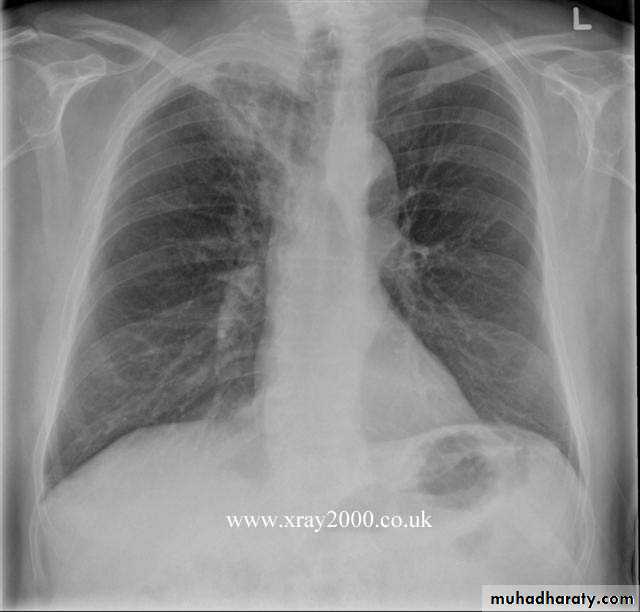

Chest radiography shows multiple pulmonary nodules of varying sizes consistent with metastatic cancer.

Chest CT scan shows multiple round nodules and masses of varying sizes in both lungs, consistent with metastases. There are also small bilateral pleural effusions.

Multiple and bilateral secondaries